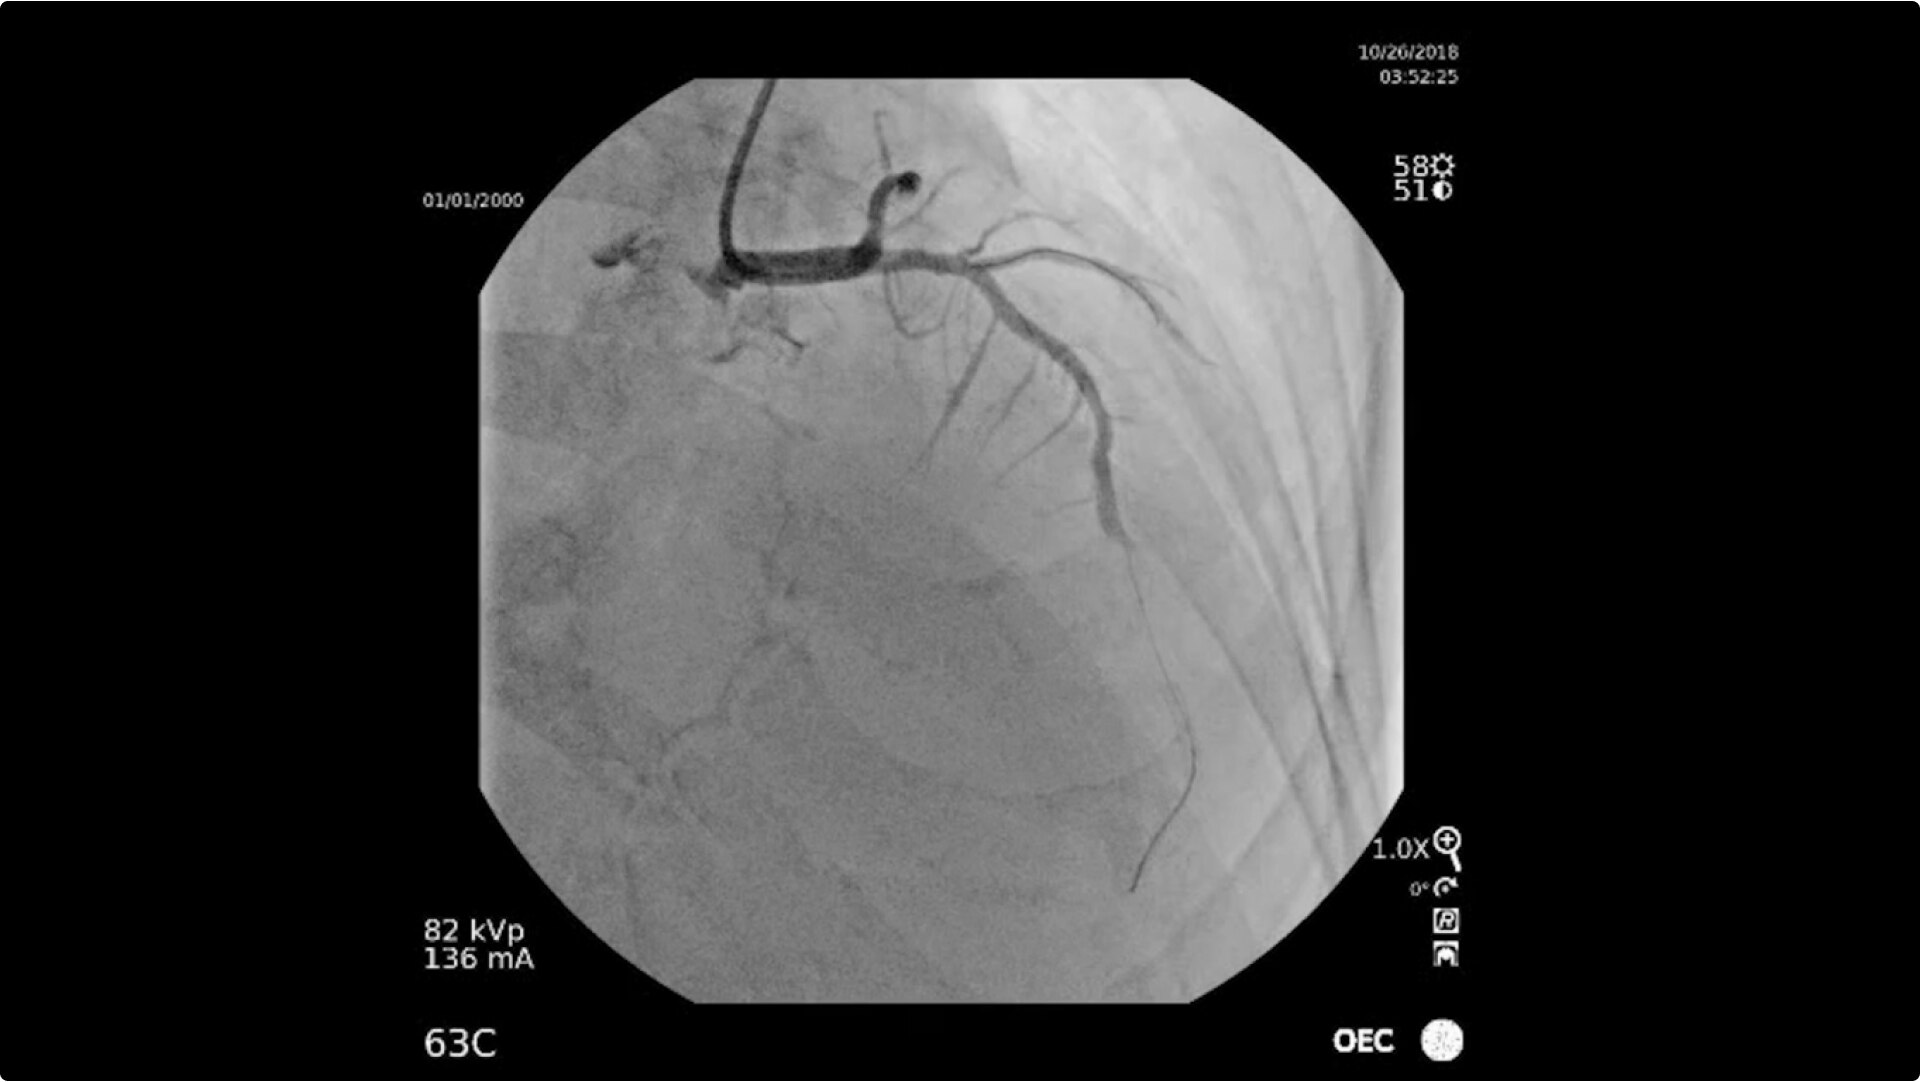

Achieve high-quality visualization necessary for complex cardiac procedures. OEC C-arms offer amazing image quality at low dose for efficient interventional imaging. Interventionalists and surgeons clearly see fine details of cardiac imaging, such as the border of the heart, leads, and small guidewires. Dynamic range management enables superb resolution, even with motion, during cardiac procedures.

See 0.014” guidewires in thoracic region or wire leads when placing biventricular pacemakers with the OEC Elite CFD flat detector, image processing, and 4K display.

To see pacemakers or coronary stenosis, Live Zoom up to 4X during a fluoro or Cine without the additional dose of Mag modes or resulting X-ray heat build up.

Cardiac imaging you need

Complex cardiac procedures require powerful imaging systems.

OEC premium C-arms perform a variety of procedures such as:

• Coronary artery diagnosis

• In-stent restenosis of coronary arteries

• Percutaneous coronary intervention